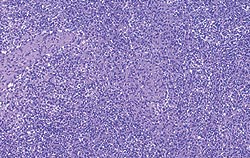

| Allure normale | Légère perturbation de l’architecture folliculaire |

| Perturbation modérée de l’architecture folliculaire | Perturbation intense de l’architecture folliculaire |

Déplétion lymphocytaire et infiltration granulomateuse légères, modérées et intenses comparées à un ganglion de structure histologique normale. Les lésions modérées et intenses sont indicatrices de la MAP. Coloration HE.